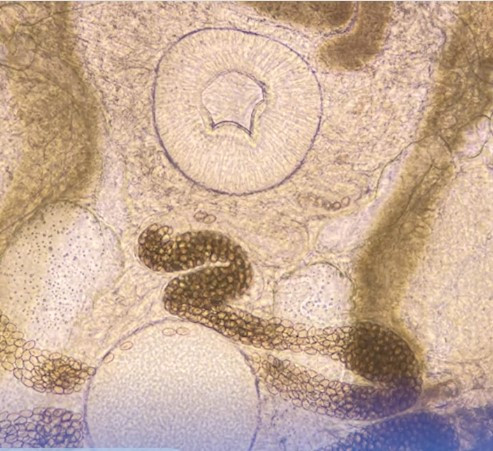

Nội soi đại tràng, phát hiện hình ảnh sán lá kích thước 5mm x 1mm, ép trứng nghi ngờ Metagonimus yokogawai.

| Nội soi phát hiện sán lá ruột nhỏ trong đại tràng bệnh nhân - ảnh BVCC |